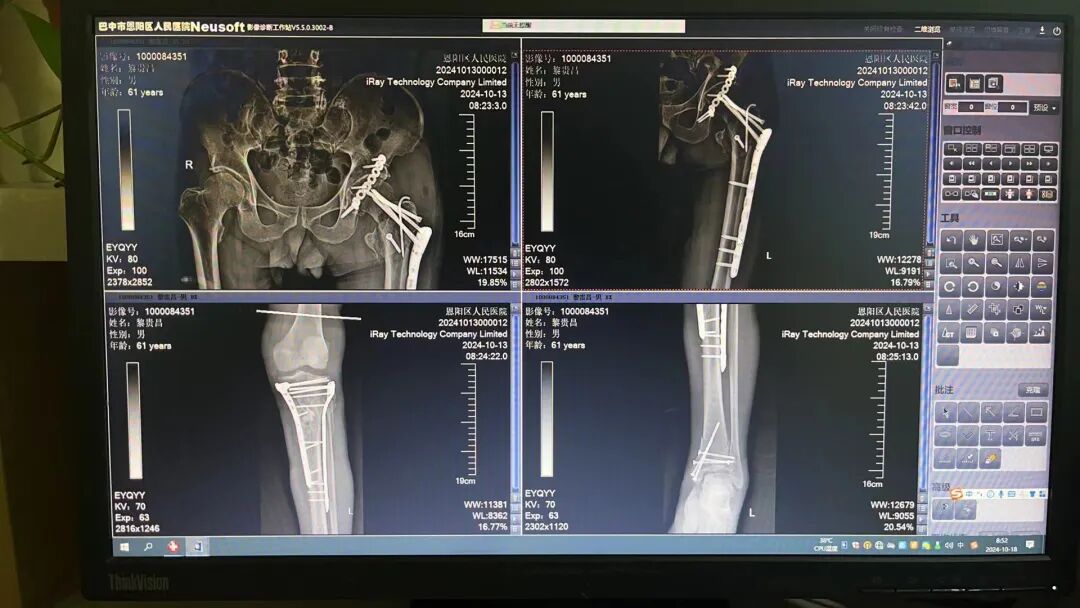

患者术后CT

图片